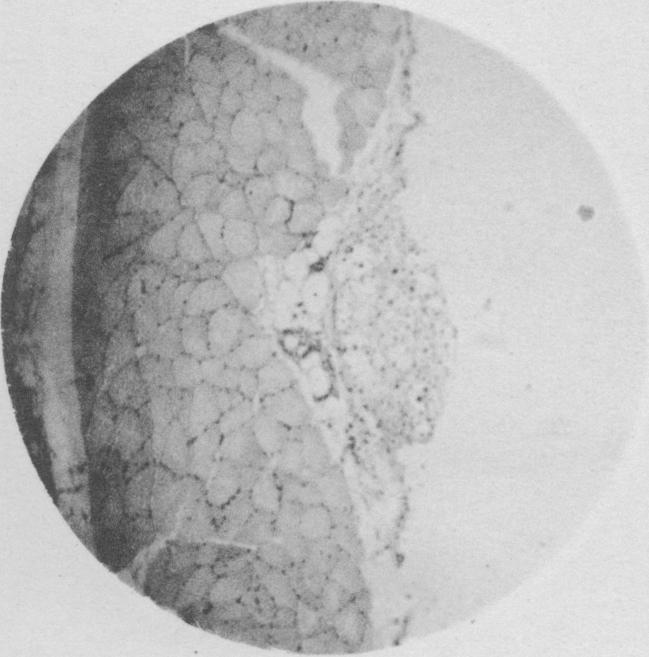

A Tumor-Like Lesion in the Lung of a Horse caused by a Blastomyces (Torula).

https://cdn.ncbi.nlm.nih.gov/pmc/blobs/a61c/2105997/e09a3557630e/jmedres00126-0053-a.jpg